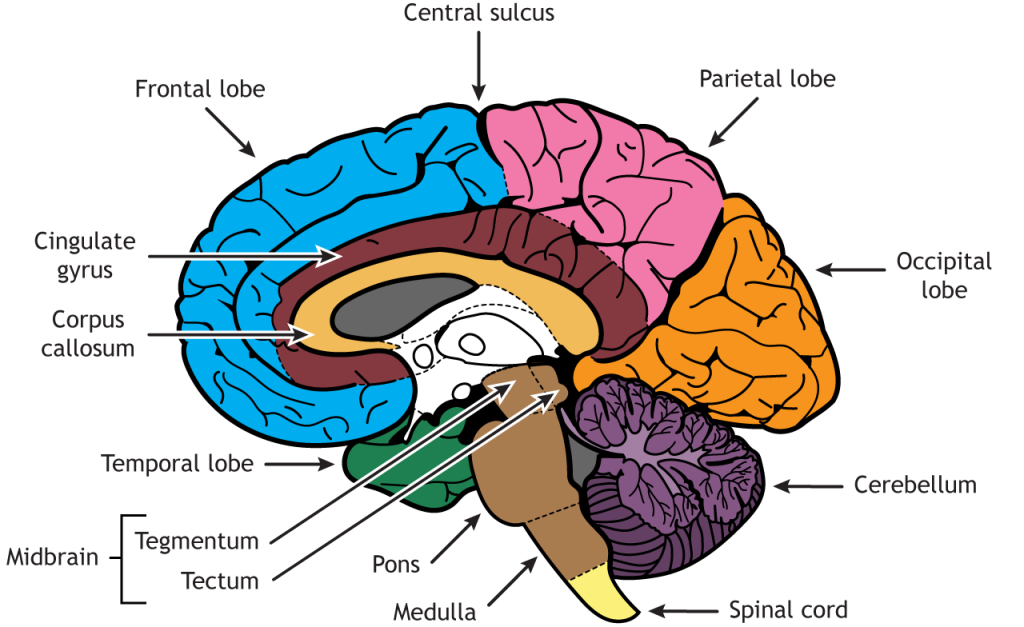

Легкие рисунки головного мозга: Пошаговые инструкции